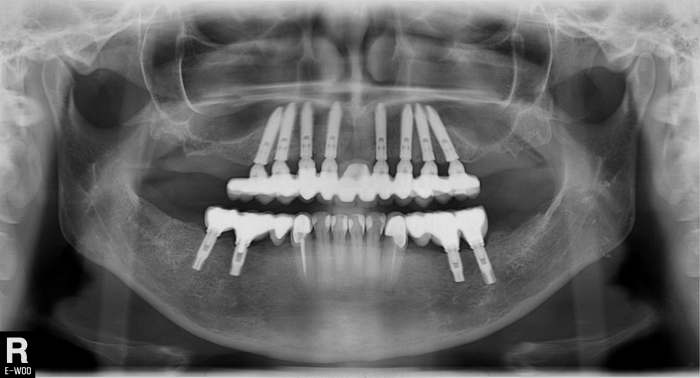

Raio X com implantes Cone Morse superiores e próteses provisórias

Raio X final